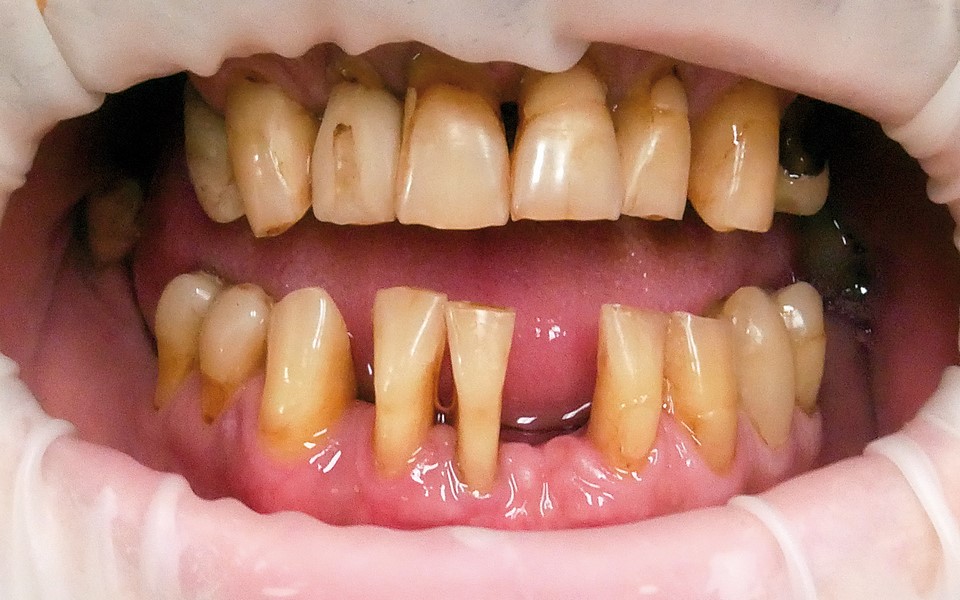

Jedną z popularniejszych metod stabilizacji zębów rozchwianych jest ich szynowanie. Metoda ta, wspierająca inne metody leczenia, jest powszechnie stosowana. Jednym z najnowocześniejszych materiałów wykorzystywanych w stomatologii do szynowania zębów jest taśma poliaramidowa. W opisanym przypadku autorzy pracy przedstawiają sposób uproszczenia całej procedury i ograniczenia ryzyka popełnienia błędu, szczególnie w sytuacji całkowitej utraty zęba. Uzyskano to dzięki zastosowaniu indeksu wykonanego z przezroczystego silikonu.

One of the more popular methods of stabilising loose teeth is to splint them. This method, aiding other methods of treatment, is generally used. One of the most modern materials used in dentistry for splinting teeth, is polyamide tape. In the case described the authors show how to simplify the whole procedure and limit the risk of making a mistake, particularly in the situation of total loss of one tooth. This was achieved thanks to the use of an index made out of transparent silicone.